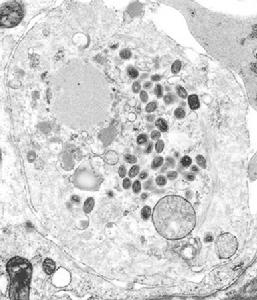

人痘接種法之一。即天花患兒的新鮮痘漿,以棉花蘸塞入被接種對象的鼻孔,以此引起發痘,達到預防接種的目的。因本法需直接刺破兒痘,病家多不願接受,故在古代亦較少用。

二是“痘漿法”,這種方法是採集天花患者身上膿瘡的漿,用棉花沾上一點,然後塞進被接種者的鼻孔;